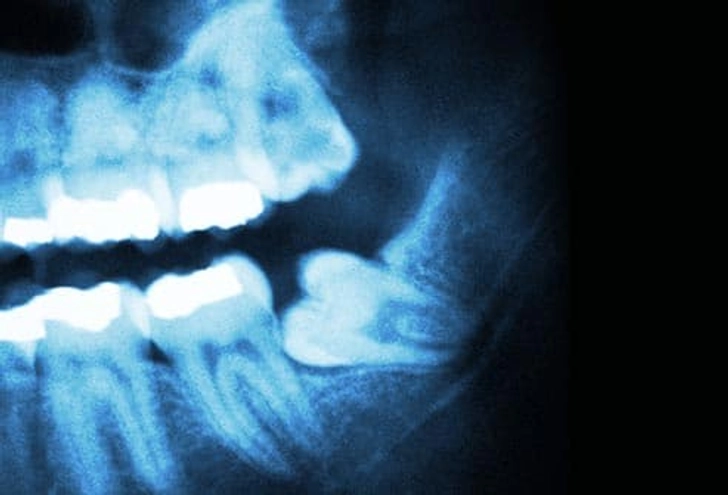

۵. دندان نهفته (Impacted Teeth)

دندانهای دائمی که درست رویش نمیکنند «نهفته» نام دارند. این حالت معمولاً وقتی رخ میدهد که دندان به دندان کناری، استخوان یا بافت نرم گیر کرده باشد. اگر مشکلی ایجاد نکند، ممکن است دندانپزشک توصیه کند همانطور باقی بماند. اما در صورت درد یا احتمال بروز مشکل، دندان توسط جراح فک و صورت خارج میشود.

📌 پیشنهاد برای مطالعه بیشتر درباره دندان های عقل نهفته: [ جراحی دندان عقل نهفته در تبریز علائم، روش های تشخیص و درمان]

۱۳. مشکلات دندان عقل

بیشتر افراد (۹۰٪) حداقل یک دندان عقل نهفته دارند. این دندانها میتوانند باعث پوسیدگی، آسیب به دندانهای کناری و بیماری لثه شوند. رویش دندان عقل معمولاً بین ۱۷ تا ۲۵ سالگی رخ میدهد. دندانپزشک باید روند رشد را پیگیری کند و در صورت مشکل، دندان کشیده میشود.

📌 پیشنهاد برای مطالعه بیشتر درباره تعرفه ها و هزینه های کشیدن : [ هزینه کشیدن دندان عقل در تبریز ]